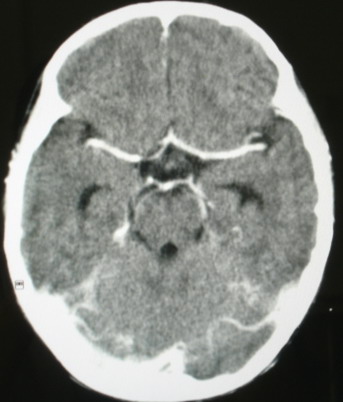

海绵窦瘘.注意眶内静脉有扩张.

右侧海绵窦血管瘤伴右侧海绵窦漏形成(由于右眼上静脉较左侧增粗。故考虑)。

支持 右侧颈内动脉海绵窦瘘.注意眶内静脉有扩张.